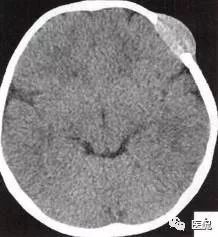

颅脑CT示:图A〜D,CT平扫示左侧额骨、蝶骨见溶骨性骨质缺损,边界清晰,周围无硬化边,伴有软组织肿块向脑外生长,边缘光滑,脑内无明显侵犯;

图E、F,横、 矢状位CT增强示软组织肿块轻度均匀强化,两病灶间亦见强化软组织影;

2.定位诊断:额骨、蝶骨均可见局限性骨质破坏,穿破颅骨内外板,见软组织肿块突向脑外;肿块与硬脑膜界限清楚,脑实质无侵犯;应考虑颅骨来源,向颅外侵犯。

②颅骨多处溶骨性破坏,穿透颅骨内外板;

③骨破坏无 硬化边,边缘光整,无膨胀;

④软组织肿块形态规则,边缘光滑;⑤脑膜及脑组织无侵犯, 表现为推压或移位。后三点均支持为良性肿块,结合年龄、实验室检查等,诊断不难。本例经病理(图I)证实为:嗜酸性肉芽肿。